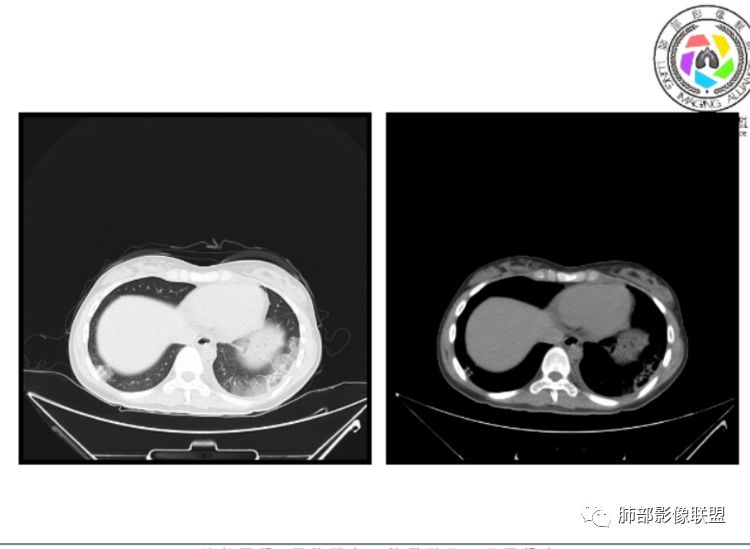

1、一个或多个胸膜下斑片高密度影(梗死、出血、肺不张、肺水肿、炎性渗出),典型为胸膜下楔形影 ,尖端指向肺门

2、肺动脉高压(中心肺动脉扩张),有时可见肺动脉区高密度影。

3、肺血减少

4、马赛克灌注

5、膈肌升高、胸腔积液、心包积液

1.临床:本例病人有服用雌激素史,是发生肺栓塞的危险因素,以胸痛起病,后有咯血症状,符合PE的临床表现;

3.影像:病变胸膜下多发斑片影,提示与血管有关,早期病变为渗出,应该是早期的炎性渗出,病灶抗感染治疗后实变区增多、变大,临床症状又出现咯血,CT上应该合并了肺泡出血、梗死、肺不张及肺水肿;

以上都高度提示肺栓塞,因积极行肺动脉成像检查!